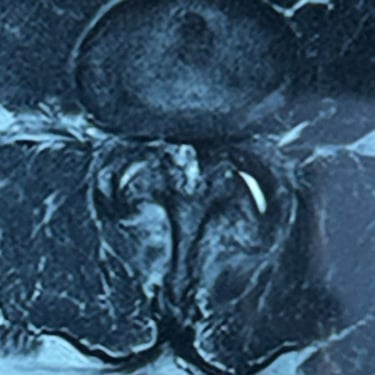

Columna lumbar inestable con listesis: tratamiento con artrodesis y tornillos transpediculares

La listesis lumbar ocurre cuando una vértebra se desplaza hacia adelante o hacia atrás respecto a la vértebra inferior, generando inestabilidad de la columna lumbar. Esta condición puede causar dolor lumbar crónico, compresión nerviosa, ciática, debilidad en las piernas o dificultad para caminar. Cuando el tratamiento conservador no es suficiente, la artrodesis lumbar con tornillos transpediculares es una alternativa quirúrgica eficaz. Este procedimiento permite fijar las vértebras afectadas mediante implantes que estabilizan la columna y favorecen la fusión ósea. Con técnicas modernas y abordajes mínimamente invasivos, se logra aliviar el dolor, mejorar la estabilidad vertebral y recuperar la función del paciente.